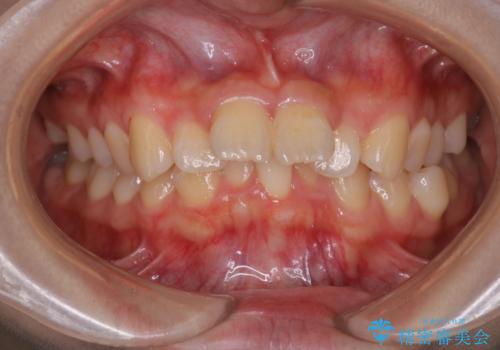

- 前歯が出ていることを主訴に来院されました。

下顎前歯が1本欠損していることもあり、前突はある程度残ることを説明し、インビザラインにて治療を行いました。

今回は抜歯矯正ではなく歯列弓の拡大とIPR、遠心移動を行って配列することができました。

口元も改善し患者さんには喜んでいただけました。